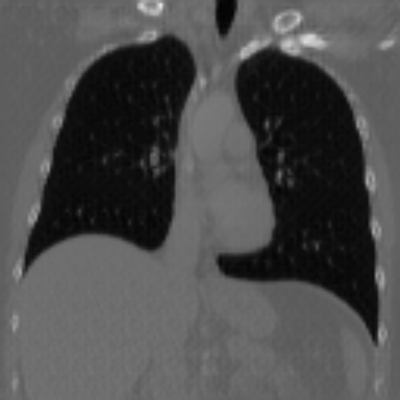

| Axial | Coronal | Sagittal | |

| X2CTGAN | ![]() |

![]() |

|

| DX2CT | ![]() |

| Ground-truth | ![]() |

Figure 3 and Table I(a) using biplanar X-rays show that proposed DX2CT can outperform three existing SOTA methods. Figure 3 shows that DX2CT can provide more accurate overall shapes and details compared to the existing methods. The quality of reconstructed CT slices in the axial plane is less satisfactory than those in the other planes. The reason is that the axial plane is perpendicular to the planes of biplanar X-rays so there exists less spatial (i.e., depth) information in the axial plane. Without using the perceptual loss [33], proposed DX2CT gave comparable LPIPS results with PerX2CTs using [33] in training. Compare their LPIPS results in Table I(a).